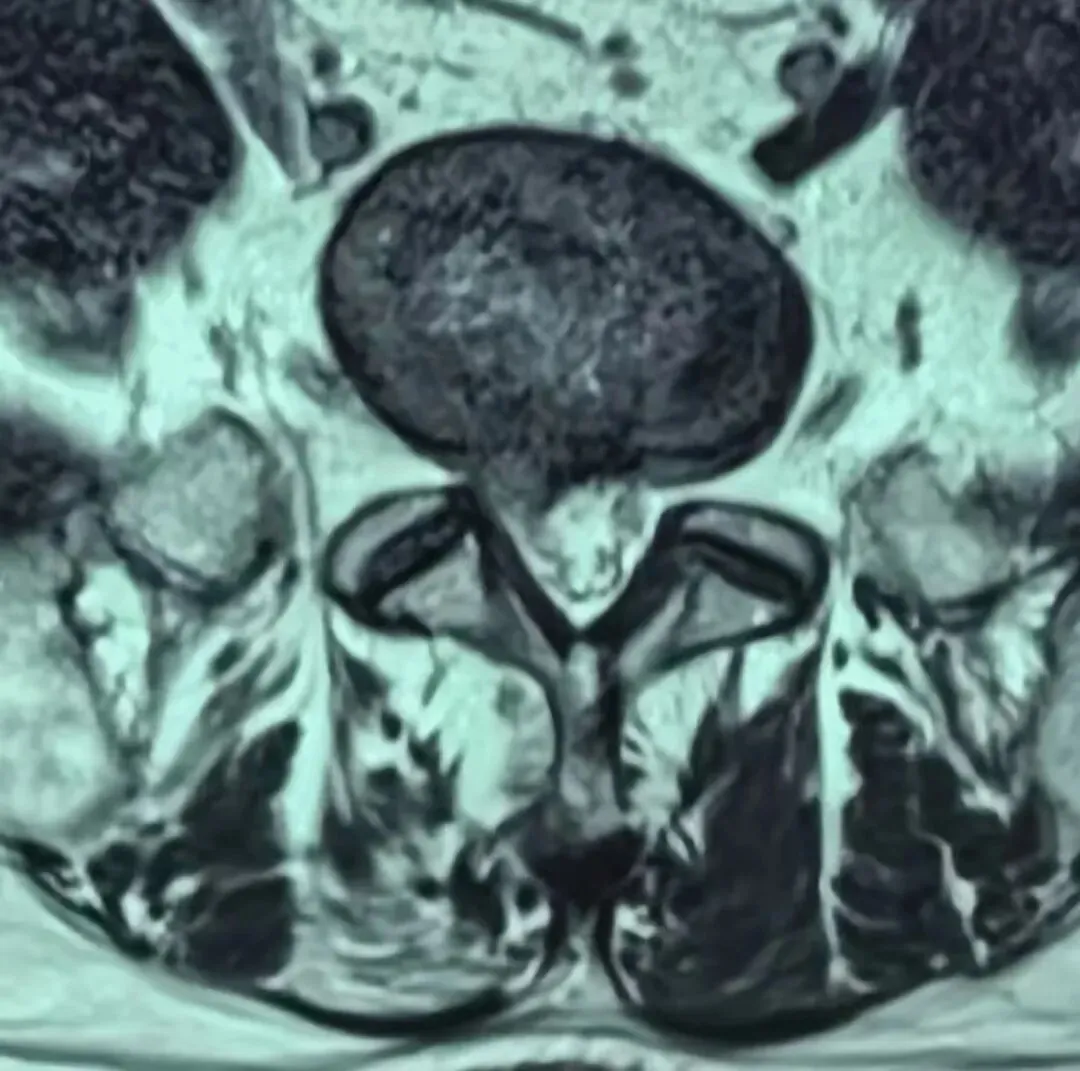

近日,我院骨科团队在外聘专家李丽教授带领下,为一位68岁腰椎间盘突出患者行经皮椎间孔镜下后路椎板减压、椎间盘髓核摘除、神经根粘连松解术。患者术后第二日便可下地行走,对骨科团队精湛医术连连点赞。

经皮全脊柱内镜后路椎板切除(减压)术、腰椎间盘突出摘除术及脊髓神经根粘连松解术属于微创脊柱核心技术,其重要性在于创伤小、对脊柱稳定结构破坏少、出血少、恢复快,可精准解除椎管、神经根压迫,避免神经缺血与功能损伤,降低术后并发症与脊柱不稳风险;有效性体现在能直接去除突出髓核、扩大椎管容积、松解瘢痕粘连,显著缓解腰腿痛、麻木、间歇性跛行等症状,神经功能恢复确切,远期疗效稳定;适应性主要针对腰椎间盘突出症、腰椎管狭窄症、神经根粘连及腰椎术后复发等病症,适用于保守治疗无效、以神经根受压为主要表现的患者,尤其适合老年及基础疾病较多、对手术耐受较差的人群。